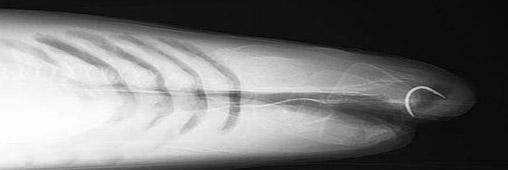

Florence est le premier requin à avoir rencontré la célébrité car le premier à avoir bénéficé d’une opération de chirurgie en Angleterre. Il s’agissait d’enlever un hameçon rouillé coincé dans le haut de sa mâchoire.

Le coté délicat de l’opération a résidé, non dans son caractère technique, plutôt simple, mais dans le dosage de précision de l’anesthésie générale. Trop ou trop peu d’anesthésiant aurait pu nuire au requin ou bien le faire refermer la mâchoire sur les mains du chirurgien.

Le requin Florence en pleine chirurgie